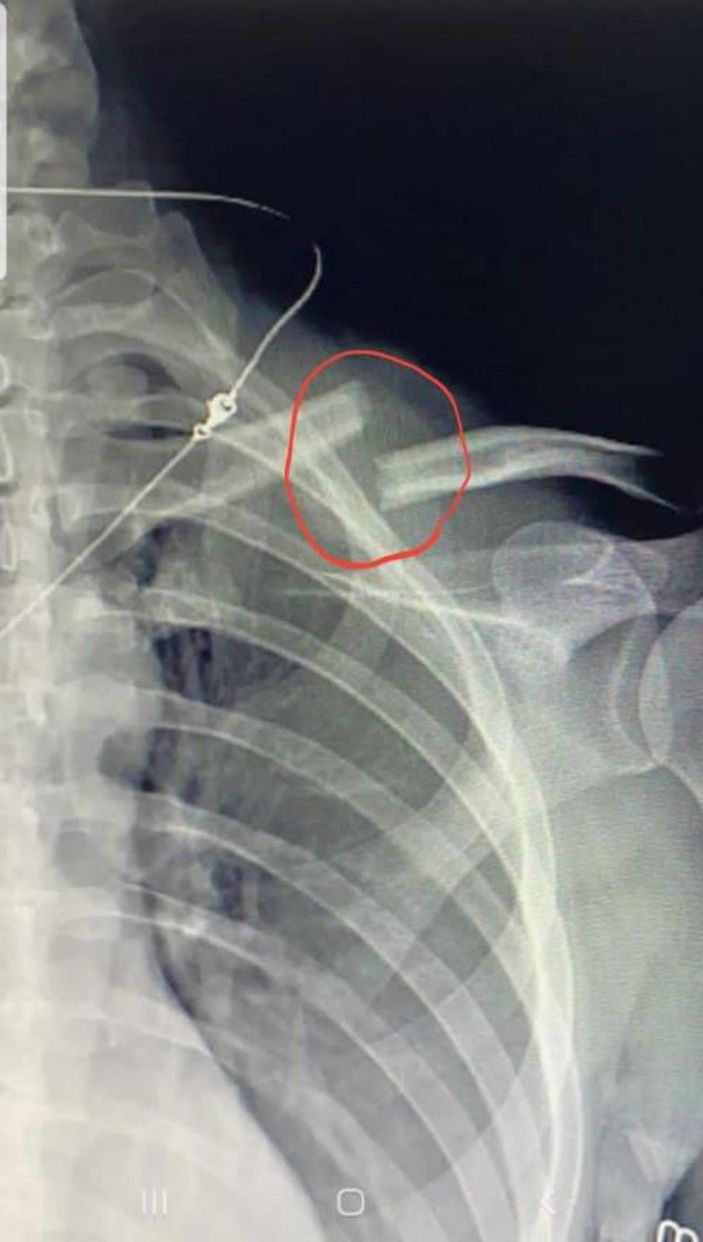

Eli yüzü kan içinde kalan kadın, gürültüyü duyarak gelen komşusu ve eski eşinin yardımıyla hastaneye götürüldü. Tedavi altına alınan Chikareva'nın köprücük kemiğinin kırıldığı belirlendi. Tedavisi tamamlanan Chikareva, darp raporu alarak eşinden şikayetçi oldu. Gözaltına alınan Salih G., çıkarıldığı mahkemece serbest bırakıldı.

Vera Chikareva, vücudundaki darp izlerini göstererek, eşine tepki gösterdi. Türkiye'ye 7 yıl önce geldiğini ve 1.5 yıl önce eşi Salih G. ile tanıştığını anlatan Vera Chikareva, "Geçen yıl ekim ayında evlenmiştim, yıl boyunca 5 kez darbedildim. Her akşam içki kullanıyor ve durmayı bilmiyor. Önceden darp raporu alıp uzaklaştırma kararı aldırtmıştım. Ama geçen hafta yine evime geldi. Burada da içki içmeye başladı. Sonra benim saçımdan tutup, duş kabinine götürdü, orada bana vurmaya başladı. Duş kabini kırıldı, ağzımda yüzümde derin izler kaldı. Vücudum tamamen kanlar içinde kaldı ve her yerim mosmor oldu. O sonra kaçtı ama ben ayakta duramadım. Köprücük köpüğüm kırılmıştı. 4 gün yattım, bir şey yiyemedim. Sonra kendime geldikten sonra karakola gittim, şikayetçi oldum, polise ifade verdim, inşallah ceza alır." dedi.